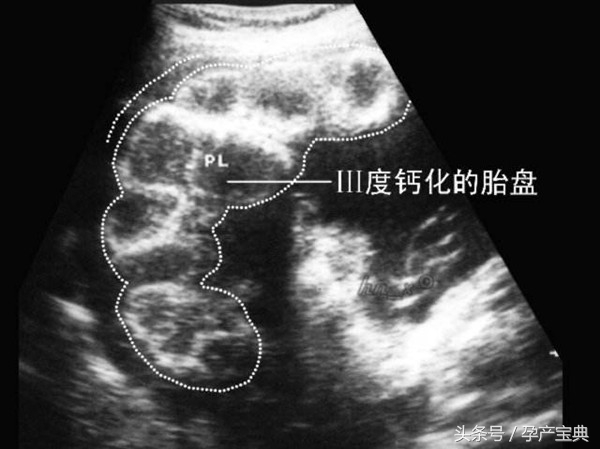

经常有孕妈妈看到B超报告单上写着胎盘Ⅰ级、Ⅱ级,甚至Ⅲ级的字样。事实上,这些都代表了胎盘的发育成熟度,Ⅰ级为胎盘成熟的早期阶段,Ⅱ级表示胎盘接近成熟,Ⅲ级则提示胎盘已经成熟。

胎盘成熟度达到Ⅲ级,就表明胎盘功能开始减退了。正常情况下,越接近足月,胎盘越成熟,而胎盘功能则随胎儿成熟逐渐下降。

如果胎盘功能确实老化了,就可能造成胎儿宫内缺氧,不仅影响胎儿的生长发育,甚至有生命危险。因此,如果发现胎盘老化,应注意严密监护,必要时采取催产或剖宫产终止妊娠。